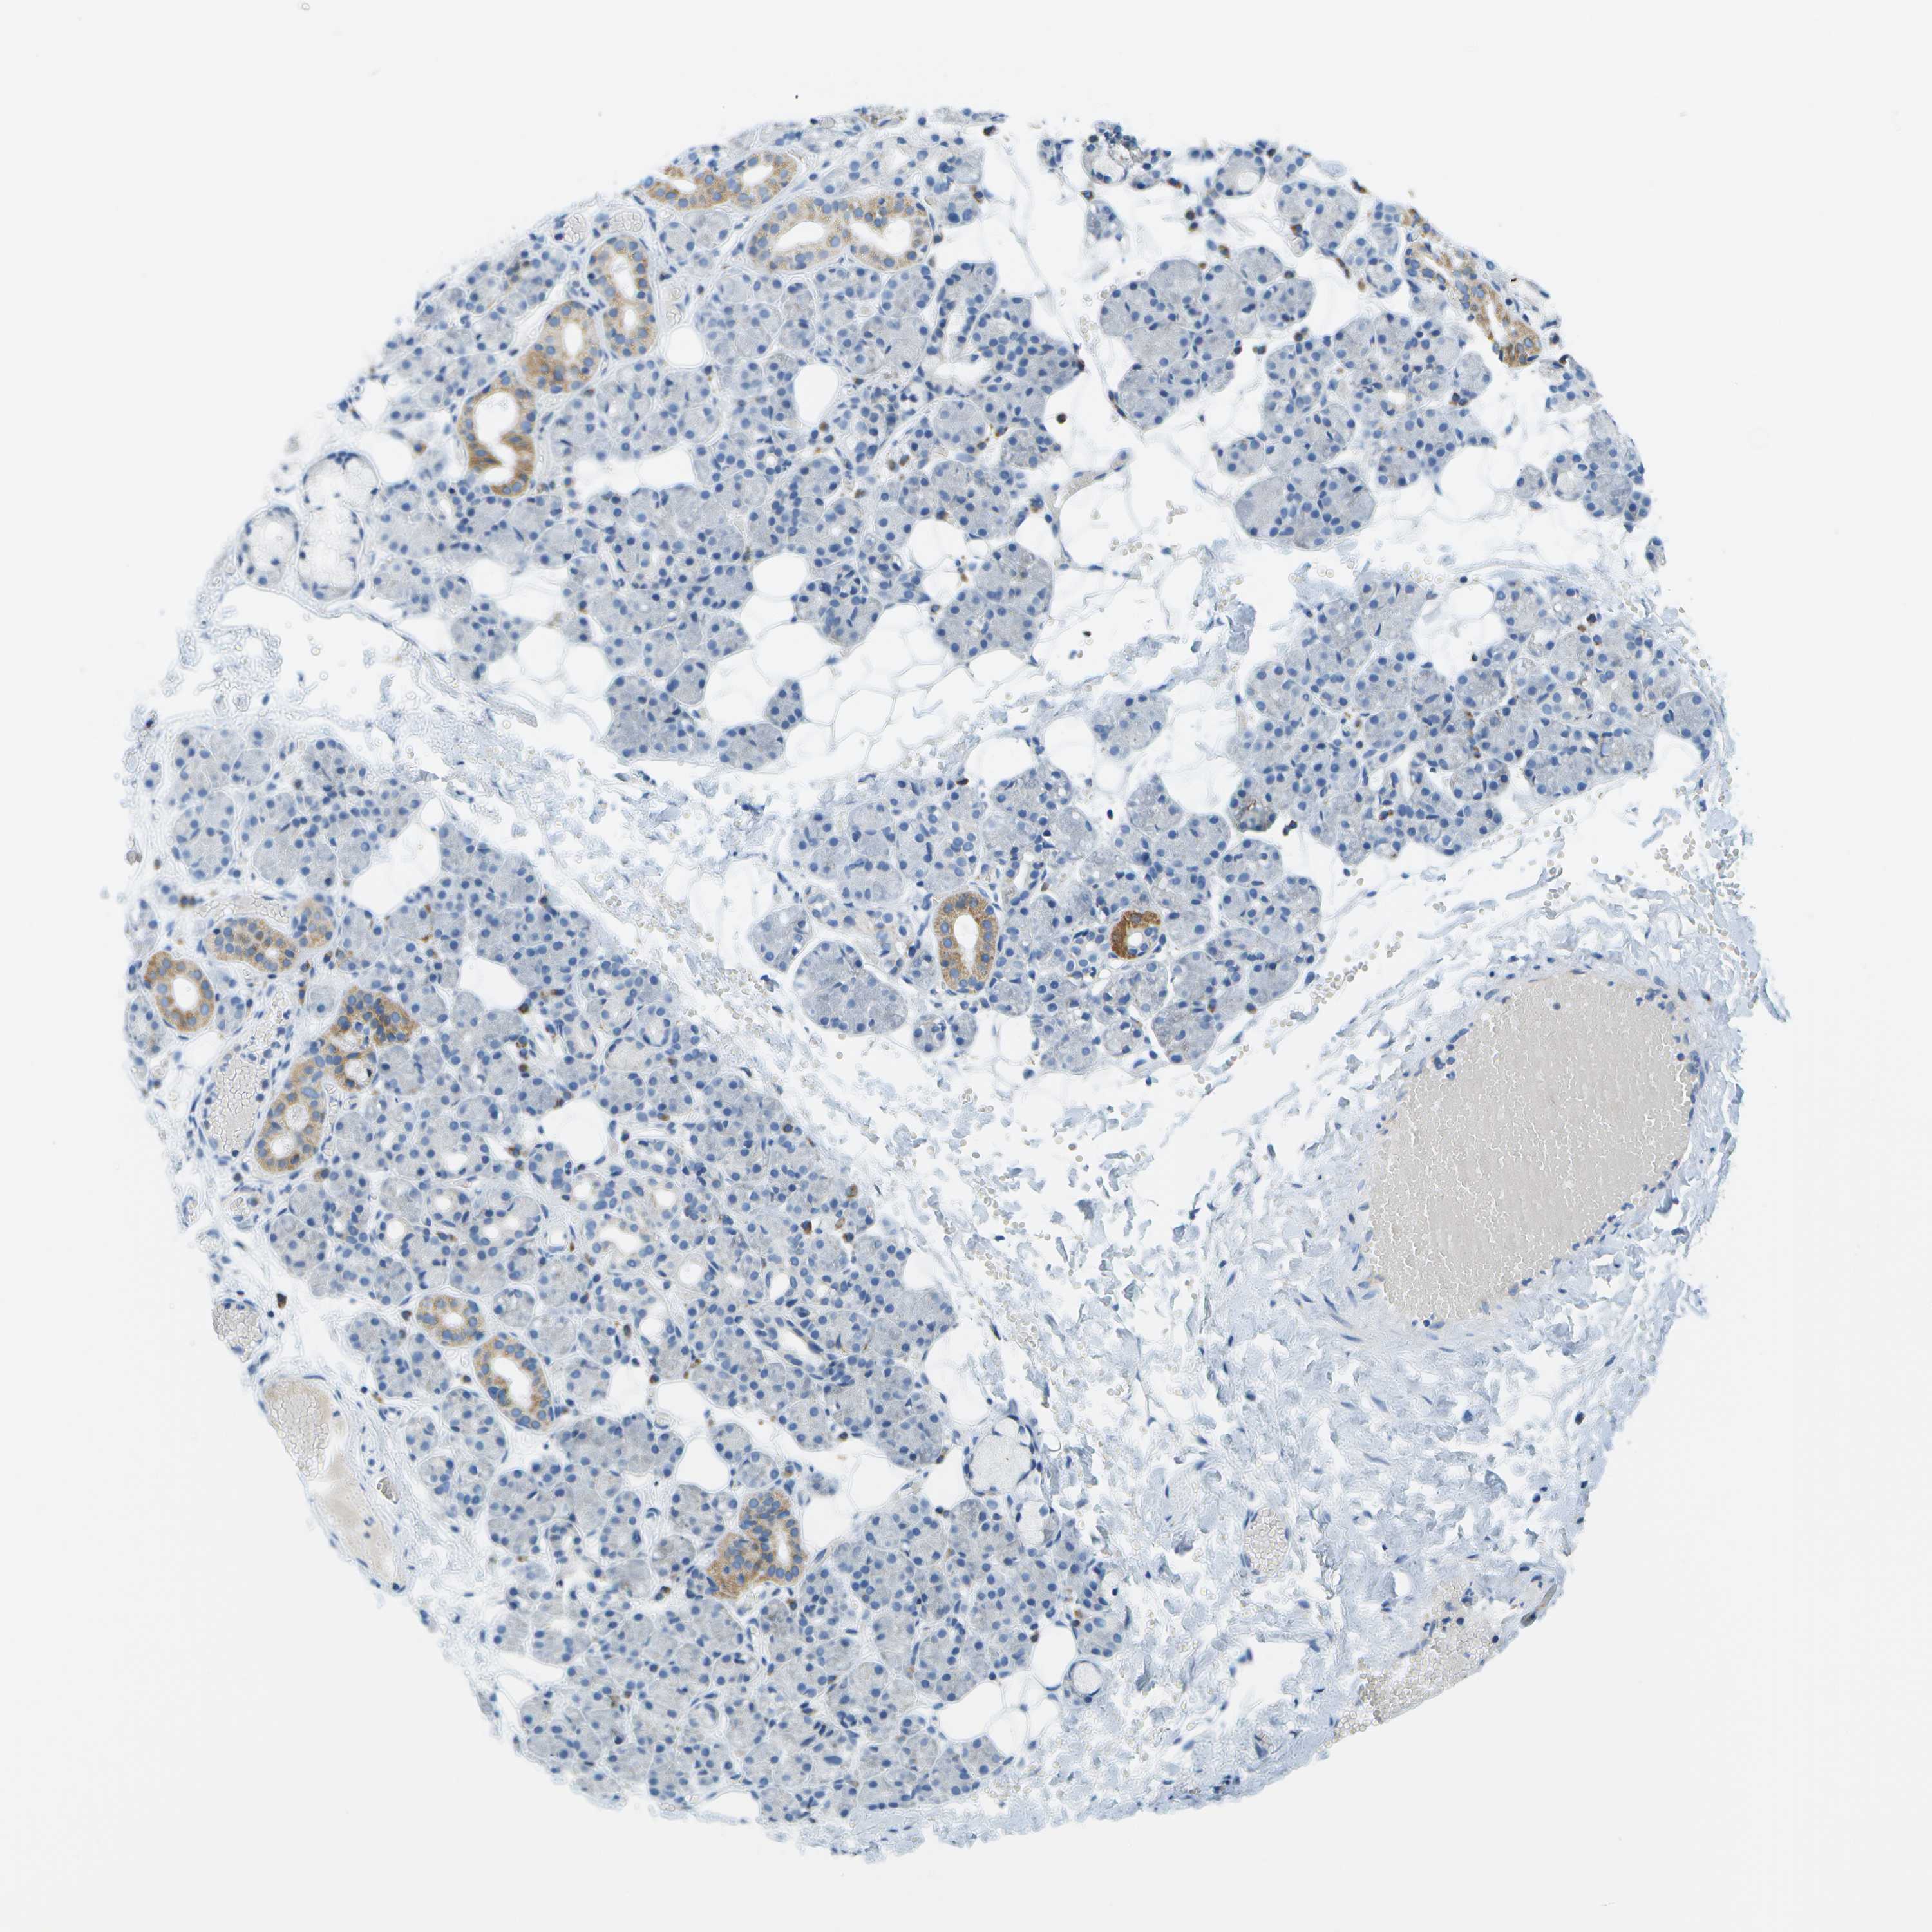

SALIVARY GLAND - HPA RNA-seqi

The RNA-seq details section shows detailed information about the individual samples used for the transcript profiling and results of the RNA-seq analysis.

Information about each individual sample is listed below, including gender, age, a tissue section image and estimated fractions of cell types. nTPM (normalized transcripts per million) values give a quantification of the gene abundance which is comparable between different genes and samples.

Average nTPMi

Max subtype nTPM is the value for the subtype with the largest average nTPM across the subtype samples.

1.5

overview

Female, age 68

Salivary gland sample 216

nTPM: 2.5

Cell types%

Glandular cells:

45

Ductal cells:

25

Adipocytes:

5

Other cell types:

Male, age 60

Salivary gland sample 217

nTPM: 1.4

55

20

Endothelial cells:

15

Female, age 21

Salivary gland sample 218

nTPM: 0.7